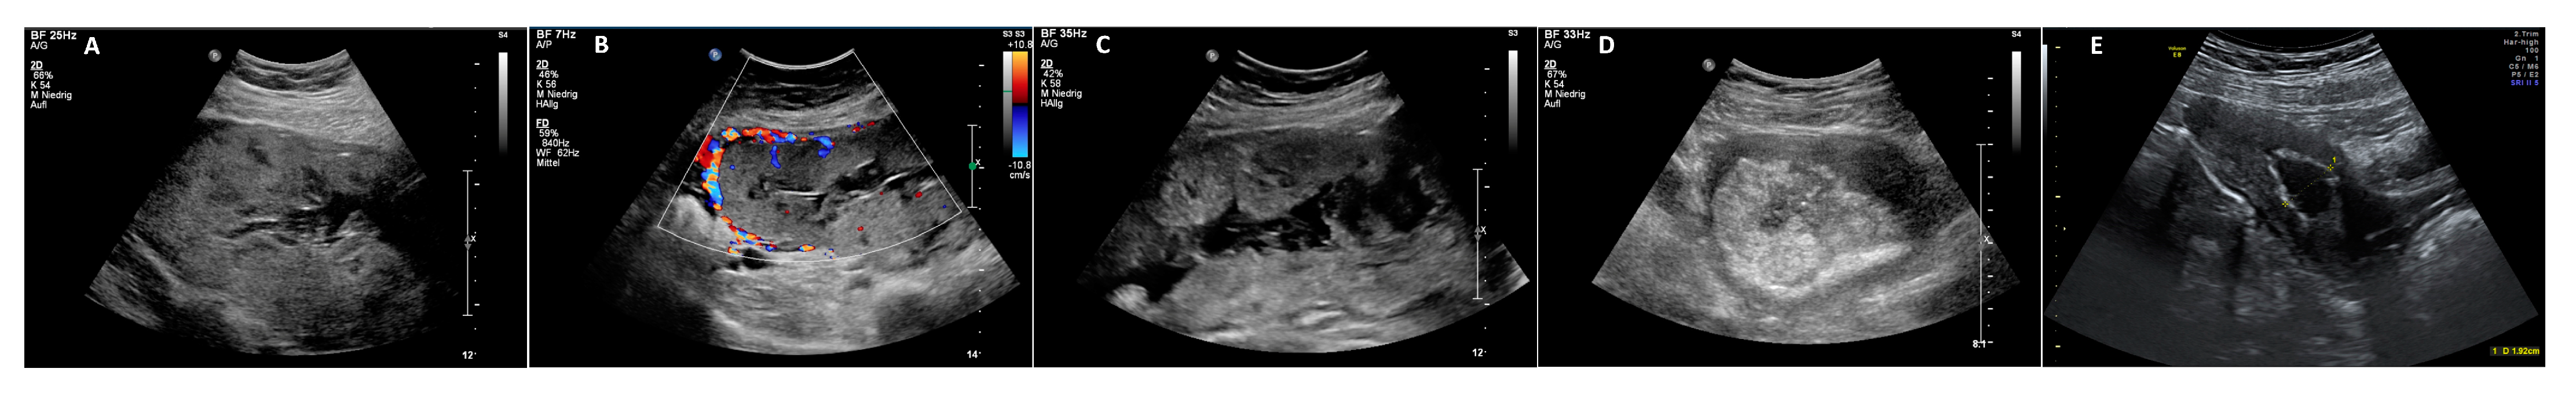

In total, two (8%) of the twenty-five patients with intended EM showed complete absorption of the retained placenta (Figure 1 and Figure 4). Fourteen patients (56%) underwent secondary curettage with complete removal of the placenta. Four (28.5%) patients received units of PRC during curettage (two, four, and eleven units). One patient presented with fever and vaginal bleeding and needed an early discontinuation of therapy due to bleeding on day 18 after CS (Table 2). An emergency curettage was performed with the insertion of a chitosan-coated gauze (Celox®). The following day, a second curettage was performed due to bleeding. This time, a Bakri balloon was inserted into the uterus. The patient received nine units of PRC and six FFP in total. Secondary HE was needed in seven patients (28%): one during CS due to severe bleeding, one due to massive intravesical bleeding because of suspected invasion of the bladder wall on day 8 after CS, one after failed placental removal during curettage on day 52 after CS, and two due to infection and perforation during curettage on days 56 and 86 after CS, respectively. Planned secondary HEs were performed in two (8%) patients, one due to a residual large area of placenta previa et increta near the cervix on day 121 after CS, and the other due to completed family planning on day 59 after CS (Table 2 and Table 3). Thus, 18 patients (72%) were successfully treated with uterus-preserving methods; in 15 (93.7%) patients, this was without severe complications (Table 1).

Figure 4.

(A) Placenta in situ on day 9 after CS. (B) Placenta in situ on day 15 after CS. (C) Regressively altered placenta in situ on day 64 after CS. (D) Placenta in situ well separated from the uterine wall without perfusion on day 106 after CS. (E) Day 194 after CS with a hyperechogenic rim around a fluid-filled uterine cavity.